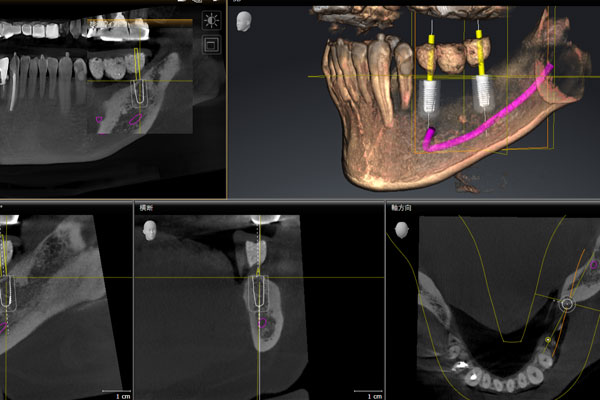

● 光学スキャンとCTによる精密な手術計画

3D光学カメラでスキャンすることで、お口の中を細部まで正確に測定し、高精細に再現することが出来ます。

歯科用CTは、神経の位置、骨の量や硬さなど、アナログでは知ることが出来なかったお口の細部の情報を正確に把握することが出来ます。

2つの機器の組み合わが精密な手術計画を可能にします。

● 3Dシミュレーション

3Dシミュレーションソフトを使用することにより、CTで得られた3D画像を元にコンピューター上でシミュレーションすることが出来ます。

インプラントの埋入位置、方向、インプラントのサイズなどを事前に決定しておくことが出来ます。

神経・血管の位置を正確に把握することは、安全性の高い手術を可能にします。